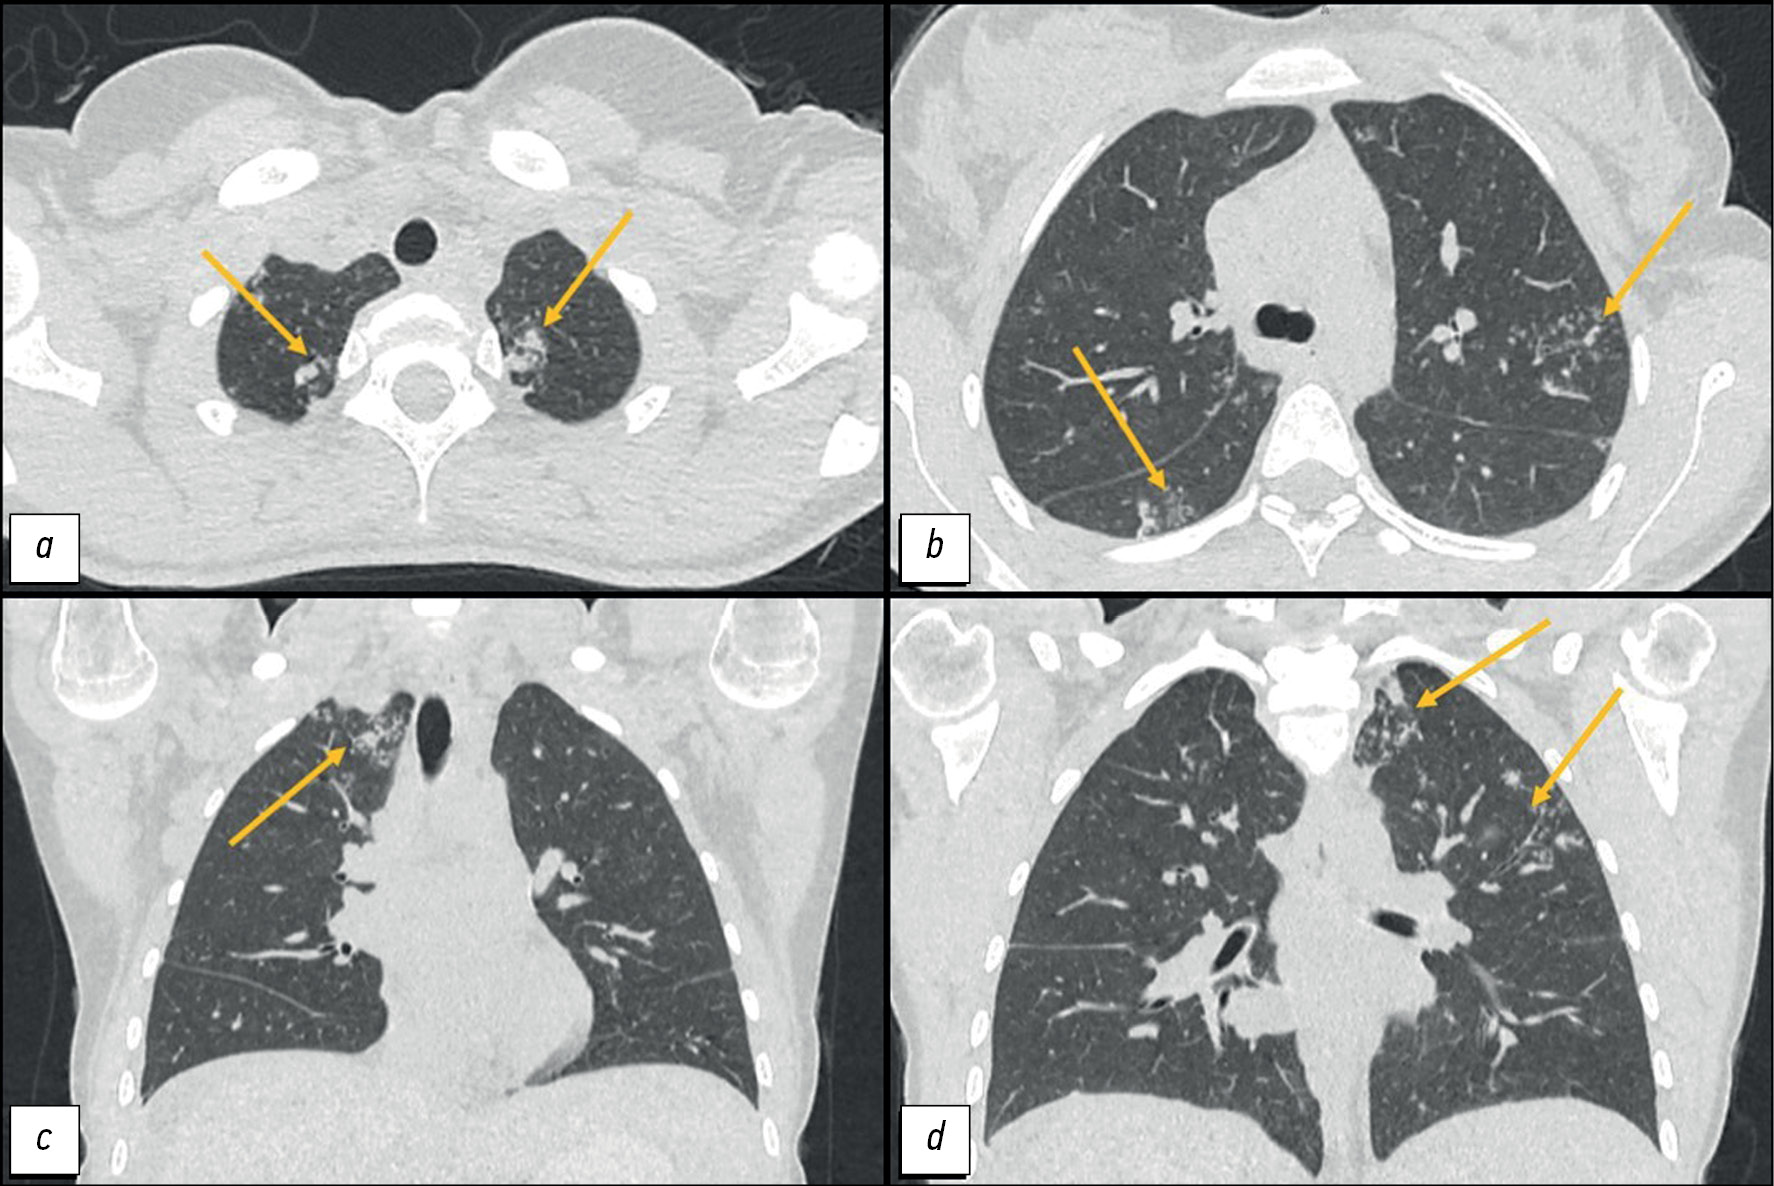

Difficulty in the differential diagnosis of peritoneal carcinomatosis and tuberculosis in a young female patient with ascites: a case report

Аннотация

The differential diagnosis between peritoneal tuberculosis and peritoneal carcinomatosis is quite challenging because of the similarity of the clinical picture and laboratory and instrumental examination data. Peritoneal tuberculosis and peritoneal carcinomatosis may present with the development of ascites, lymph nodes, and intestinal loop conglomerates. This article presents the clinical case of a young patient who, after her second childbirth, noted the appearance of intense pain in the neck and between the scapulae. Two months later, she experienced pneumonia with a positive reaction to antibiotic therapy. After another 2 months, she experienced recurrent ascites and gastrointestinal symptoms for the first time. The examination revealed ovarian masses and signs of peritoneal carcinomatosis and lung nodules. However, the clinical presentation was atypical for peritoneal carcinomatosis, and lung lesions were suspicious for tuberculosis, which allowed us to hypothesize the presence of tuberculosis of multiple localizations. The diagnosis was confirmed by laparoscopy with a biopsy of the involved tissues and subsequent histological and laboratory confirmation of the etiological role of Mycobacterium tuberculosis. The described case demonstrates the importance of using all available diagnostic methods to establish the causes of ascites in young female patients for differential diagnosis between specific and neoplastic etiologies.